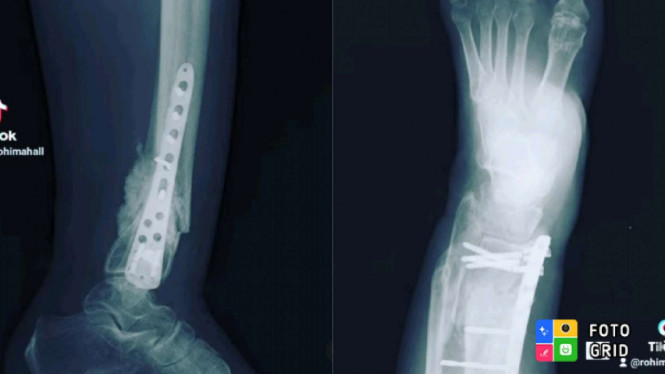

Selama di Istanbul, Turki, Rohimah merasakan sakit luar biasa pada kakinya yang pernah patah dan dipasang PEN. Namun tak disangka ternyata mur pada pen di kakinya copot dan akhirnya harus menjalankan operasi.

Mirisnya, mur yang copot itu hingga mengenai daging dan urat pada kakinya. Sehingga menimbulkan rasa sakit yang luar biasa dan tak bisa tergambarkan.